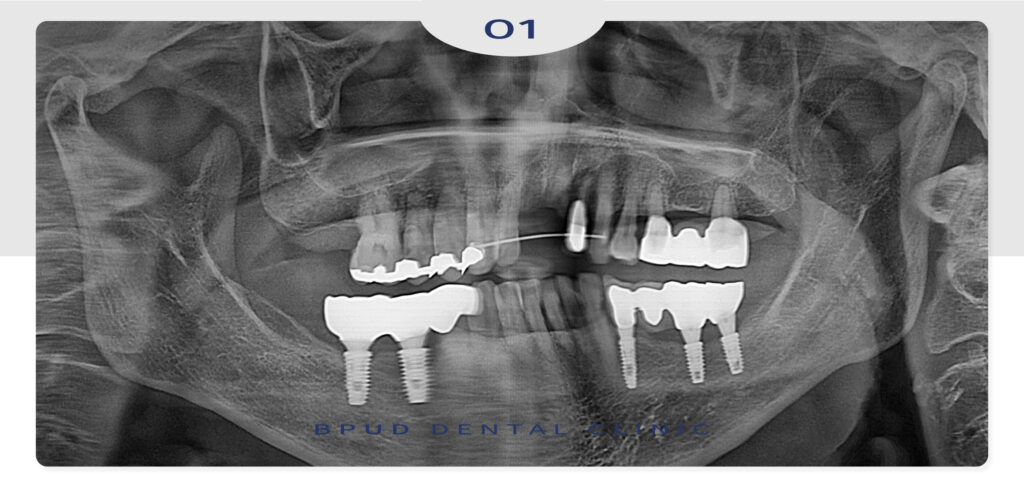

내원 전날 넘어지셔서 치아가 부러진 것을

확인하고 응급실에 내원하여 응급처치로

철사로 제작된 스프린트를 장착하고 계신 상태였습니다.

오른쪽 앞니는 완전히 빠진 상태였고

옆쪽 치아는 치근만 남아 있는 상태,

응급실에서 스프린트를 처치 받았으나

양쪽 옆 치아들도 동요도가 보이는 상태로

외상 후 최소 2주간은 스프린트를 유지해야함을

설명드리고 이후 내원할 수 있도록 안내드렸습니다.